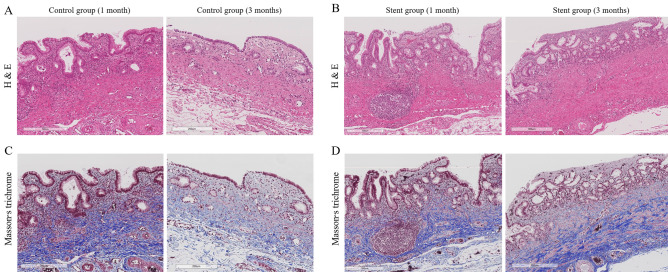

Histopathology

Because the tissue response could vary depending on the duration of stent placement, three pigs that lost their stents during the follow-up period were excluded from the histopathologic analysis. Therefore, histopathological examination was performed on CBD specimens obtained from 11 pigs (control group, n = 3; stent group, n = 8). The stent group showed significantly higher scores for mucinous gland hyperplasia, lymphoplasmacytic infiltration, and total tissue inflammation (P < 0.05) (Table 2; Fig. 8). There were no significant differences in epithelial hyperplasia or neutrophil infiltration between the stent and control groups. In addition, Masson’s trichrome staining showed thicker fibrosis in the stent group than in the control group (0.46 ± 0.12 mm vs. 0.21 ± 0.05 mm, P = 0.012) (Table 2; Fig. 8). Regarding the stent group, there was no difference in total tissue inflammation scores between the 1-month follow-up and 3-month follow-up groups (6.0 ± 2.65 vs. 5.4 ± 1.95; P = 0.763). In addition, there was no significant difference in fibrosis thickness between stent groups at the 1- and 3-month follow-up.

In terms of histopathology, although the stent group had significantly higher scores for mucinous gland hyperplasia and lymphoplasmacytic infiltration than those of the control group, the stent group’s scores also suggested mild-to-moderate inflammation. These results are consistent with those of a previous animal study using PDO biliary stents17, which showed mild-to-moderate inflammation during a 20-week follow-up period. In addition, fibrosis in the stent group was significantly thicker than that in the control group. According to another previous animal study using PDO biliary stents22, the degree of fibrosis in the control group was more marked than that in the stent group at the duct-to-duct biliary anastomosis site. However, in that previous study, the fibrosis thickness of the control group was 3.84 mm, which was significantly thicker than that of our study’s stent group (0.46 mm). Even the thickness of fibrosis in the stent group in our study was less than that of the control group (0.68 mm) in that study. Therefore, although there was a difference in fibrosis thickness between the control and stent groups in our study, the degree of fibrosis in the stent group was minimal. Furthermore, according to previous studies29,30, mild inflammation and fibrosis in the porcine bile duct that did not cause problems such as biliary obstruction or leakage were interpreted as acceptable in terms of safety and feasibility.